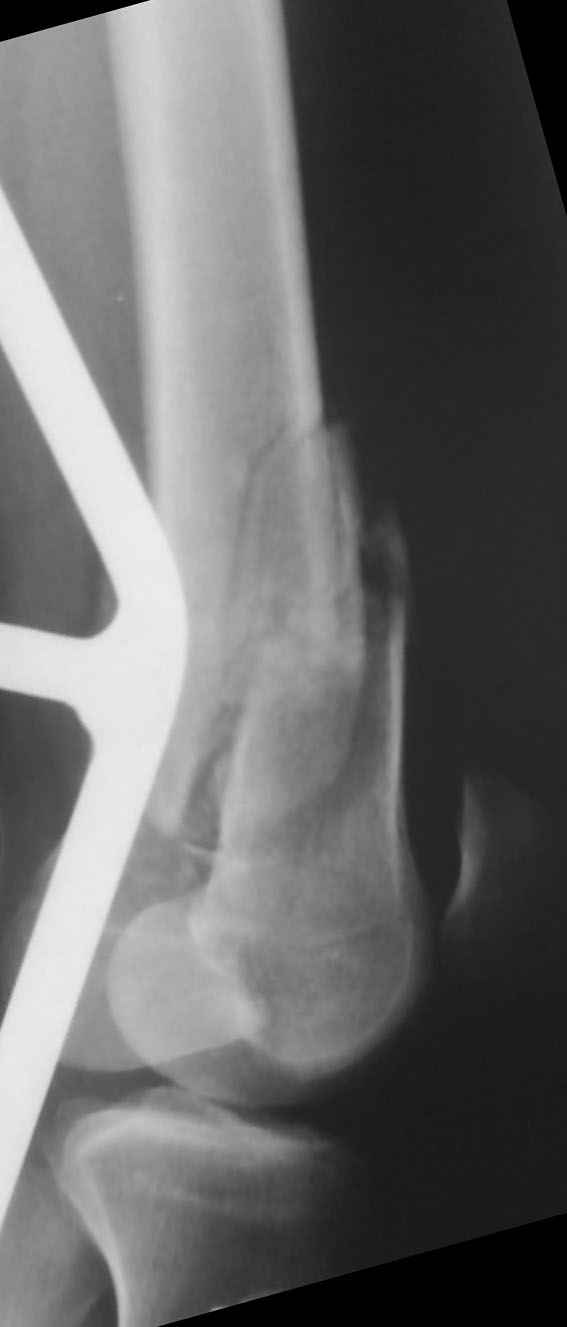

К нам поступил пациент 25 лет с закрытыми переломами обеих бедренных костей, прошел месяц после травмы.

Слева - внутрисуставной перелом, поэтому выбор здесь очевиден, открытая репозиция, стабильная фиксация, скорее всего LCP DF, а справа - мнения учёных, как говорится, разошлись. Лично я, как лечащий врач, за закрытый интрамедуллярный остеосинтез DFN. Со мной согласна половина коллектива, другая - за интрамедуллярный остеосинтез (DFN,UFN) но с открытой реопозицией, поскольку при закрытой методике все осколки останутся где-то сбоку, получится дефект и вдруг не срастется!

Философский вопрос: что лучше - красивая рентгенограмма или сохранение кровоснабжения? Очень важно мнение коллег!